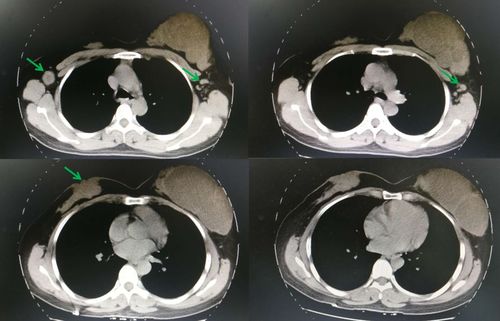

乳腺癌ct片图片,乳腺癌切除图片

我妈妈乳腺癌术后10个月做的胸部ct,能帮忙看一下情况

bc青年团|岳文杰:乳腺癌合并对侧交界性叶状肿瘤病例

复查-乳腺癌患者互助回答-觅健